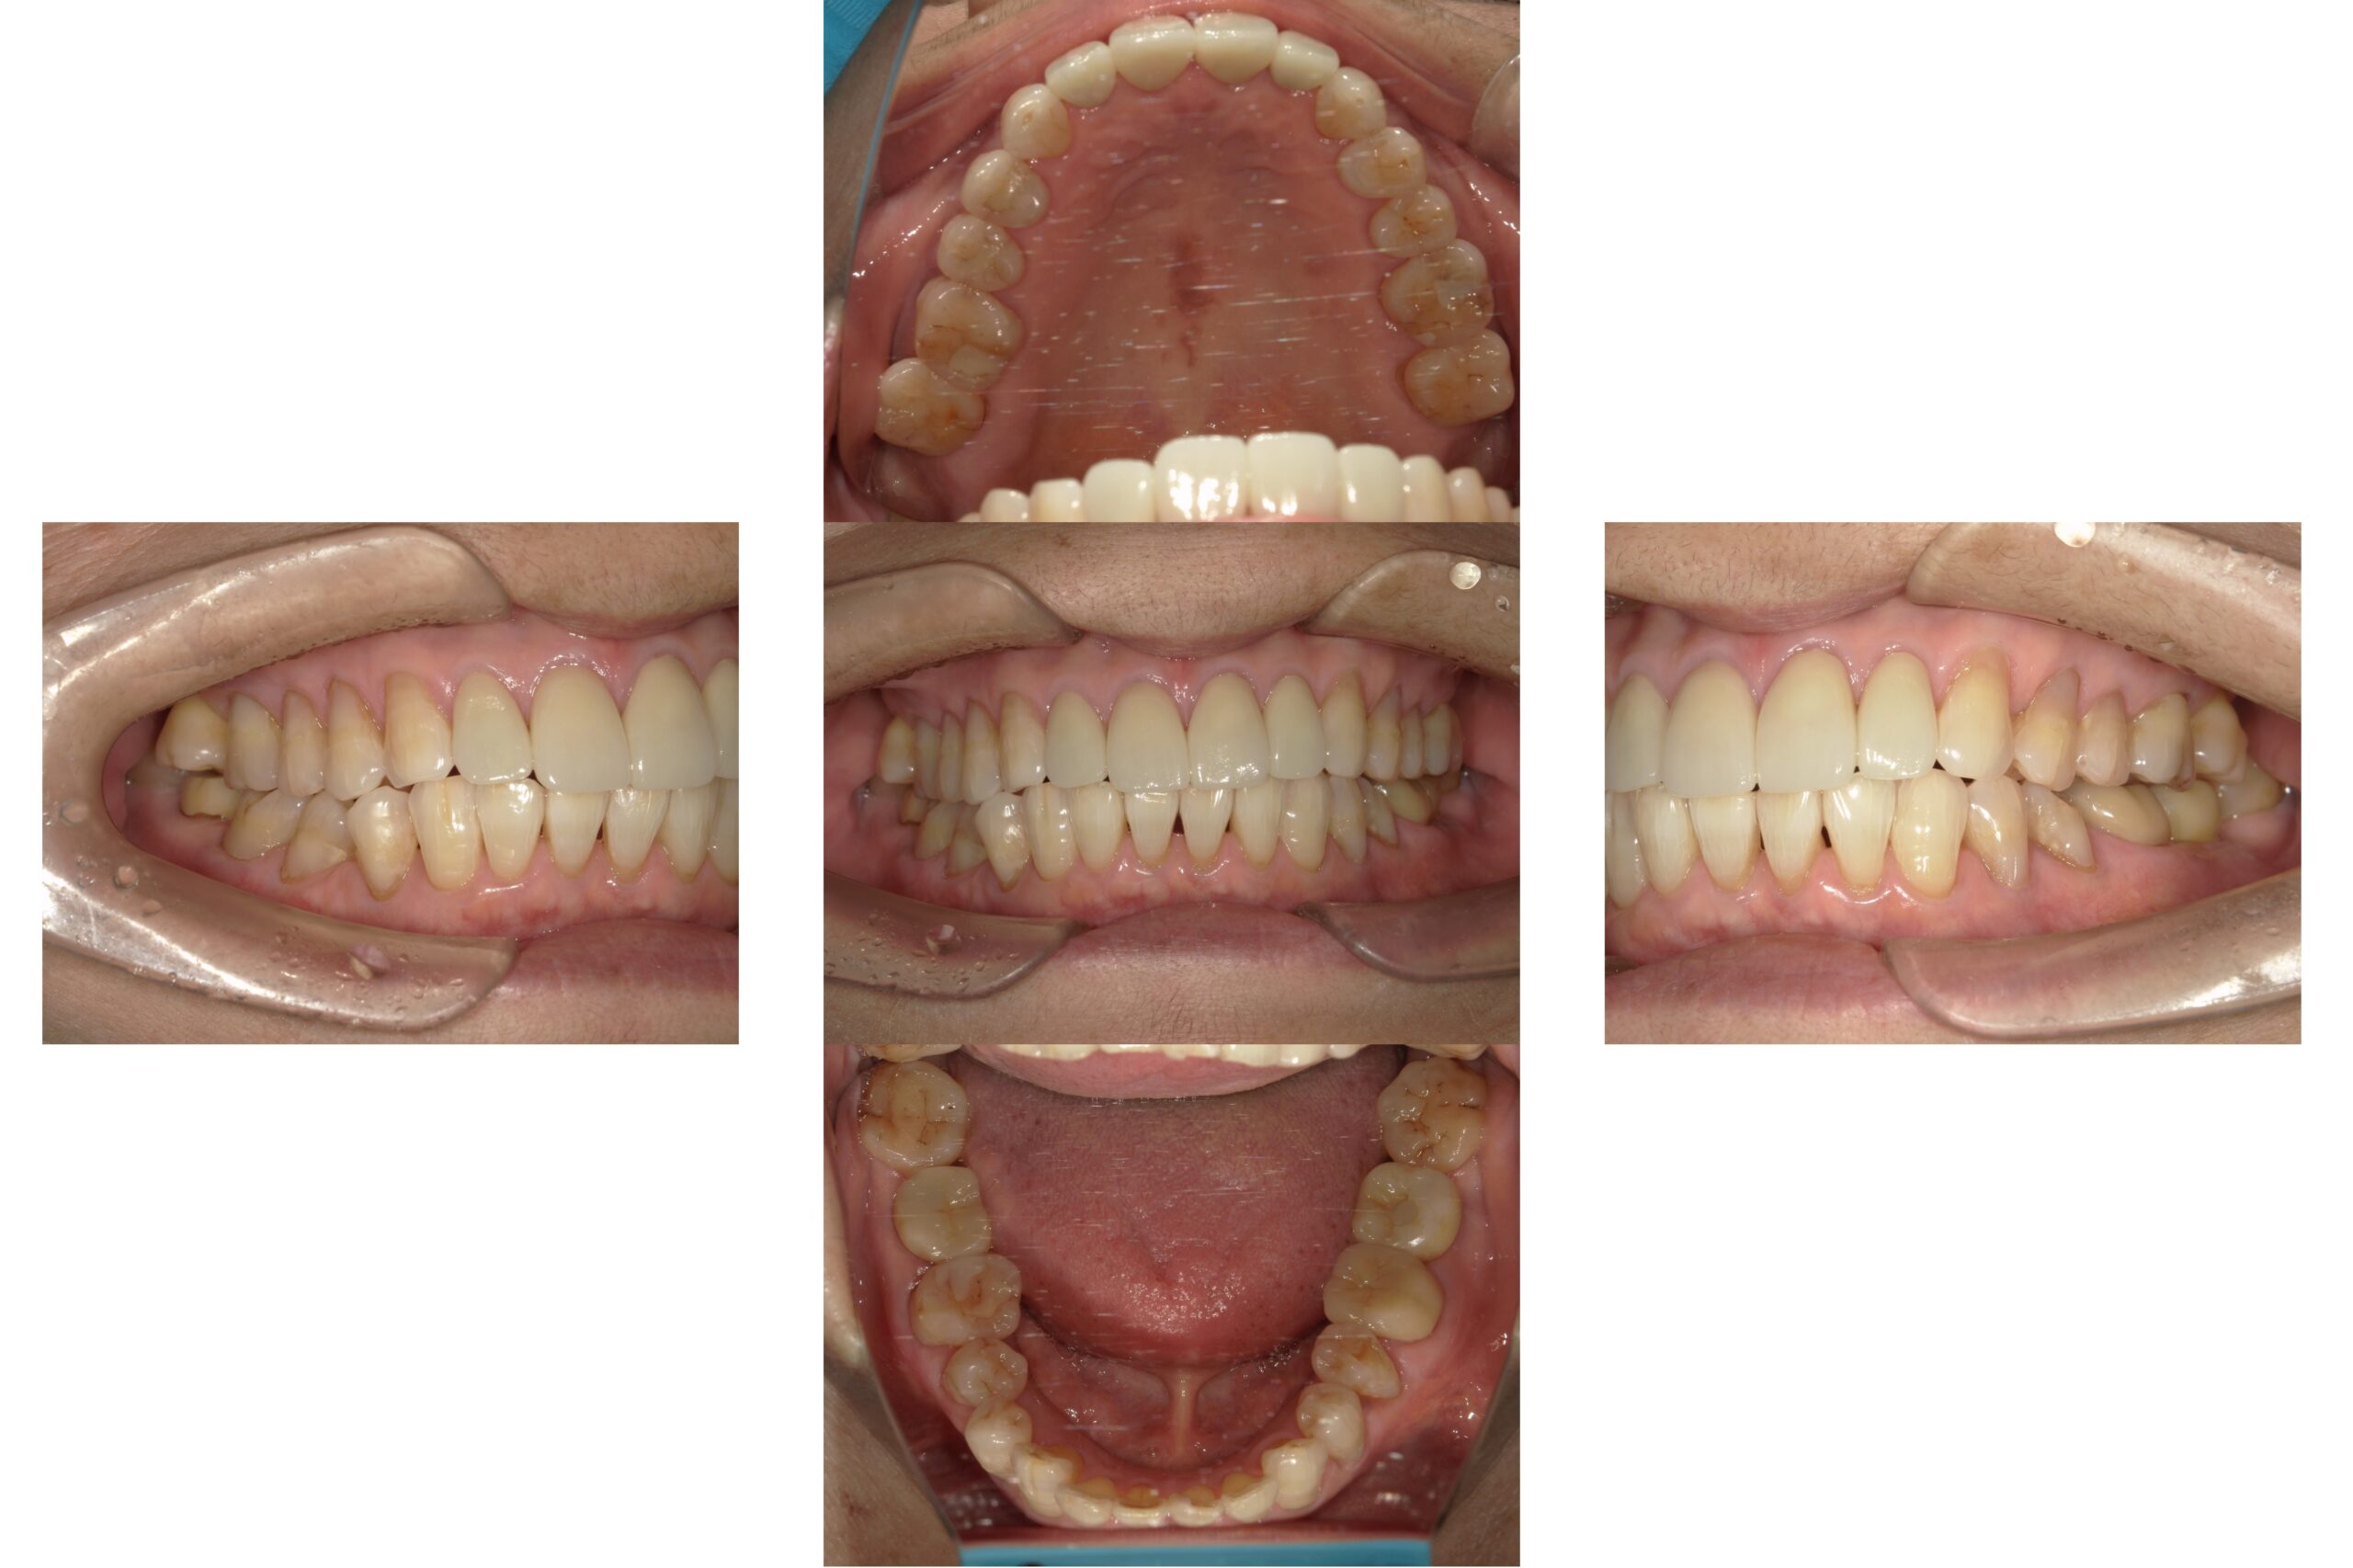

オープンバイト(開咬)のマウスピース矯正治療

Before

After

年齢

52歳

主訴

前歯でものが噛みきる事が出来ない。

治療期間

約2年

治療費

マウスピース型矯正装置 税込990,000円

治療内容

前歯でものを噛みきることが出来ず、年を取るにつれ奥歯が悪くなってきた気がするとのことでした。

ご相談させていただき、歯を抜かずにマウスピース矯正にて矯正治療を行わせていただきました。

治療期間は2年かかりましたが、見た目だけでなく前歯でしっかりものを噛めるようになり大変満足して頂けました。